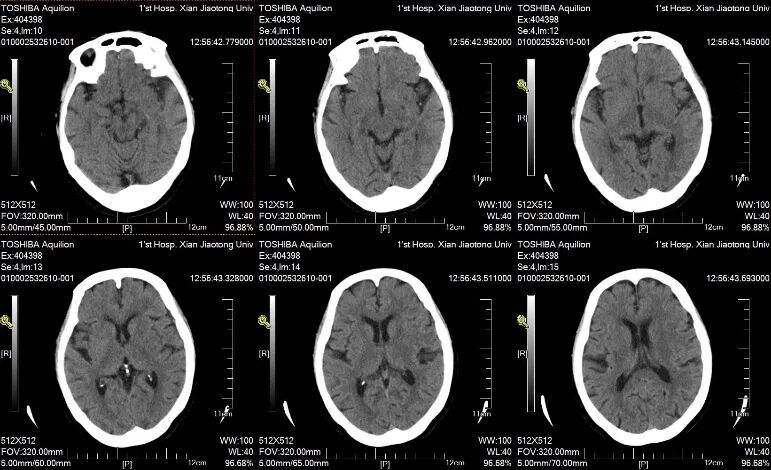

术后即刻NCCT:左侧侧脑室旁基底节区造影剂外渗;

术后6小时NCCT

术后24小时NCCT